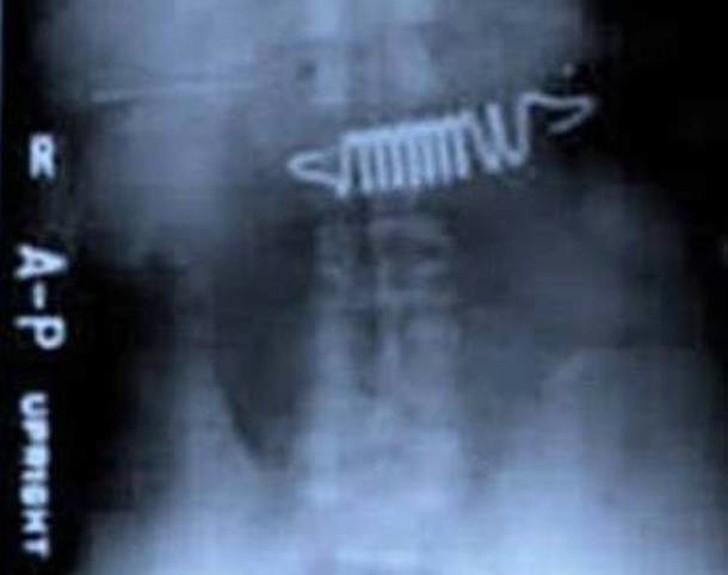

19. Пружины от кровати.